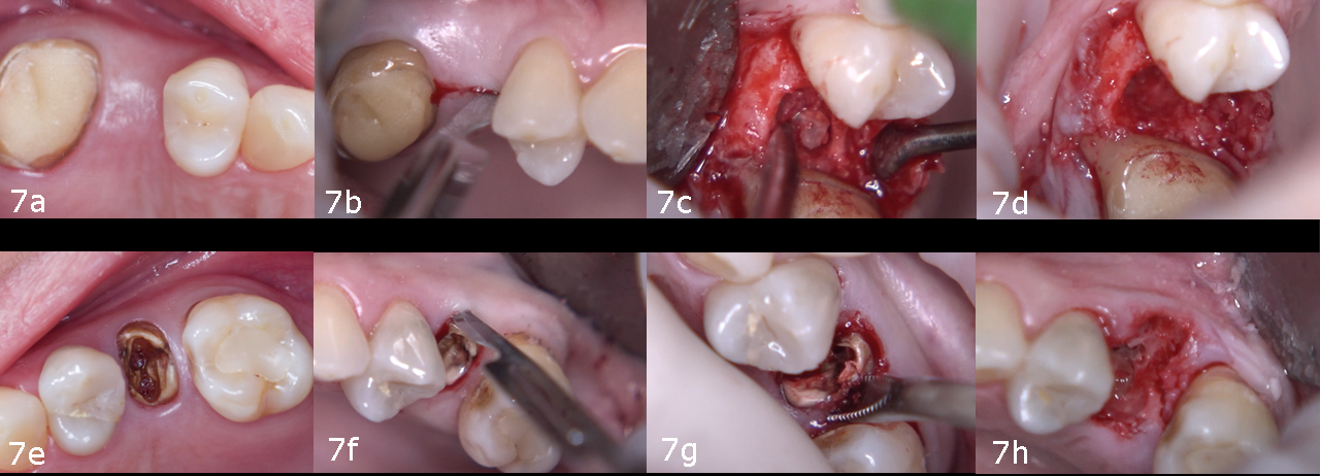

Under local anaesthesia administered bilaterally, the surgical procedure began at site #15 with a supra-crestal incision and a full-thickness flap to ensure full visibility of the area for the location and extraction of the residual root previously identified on the CBCT scan. The root fragment was located and extracted without complication. At site #25, a minimally traumatic, flapless extraction was performed using a periotome, followed by the use of forceps to gently remove the root (Figs. 7a–h).